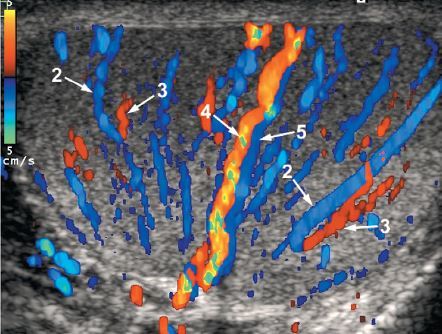

1

1. capsular artery

2. centripetal artery

3. recurrent artery

4. transmediastinal artery

5. transmediastinal vein

• capsular artery

• centripetal artery

• recurrent artery

• transmediastinal artery

• transmediastinal vein